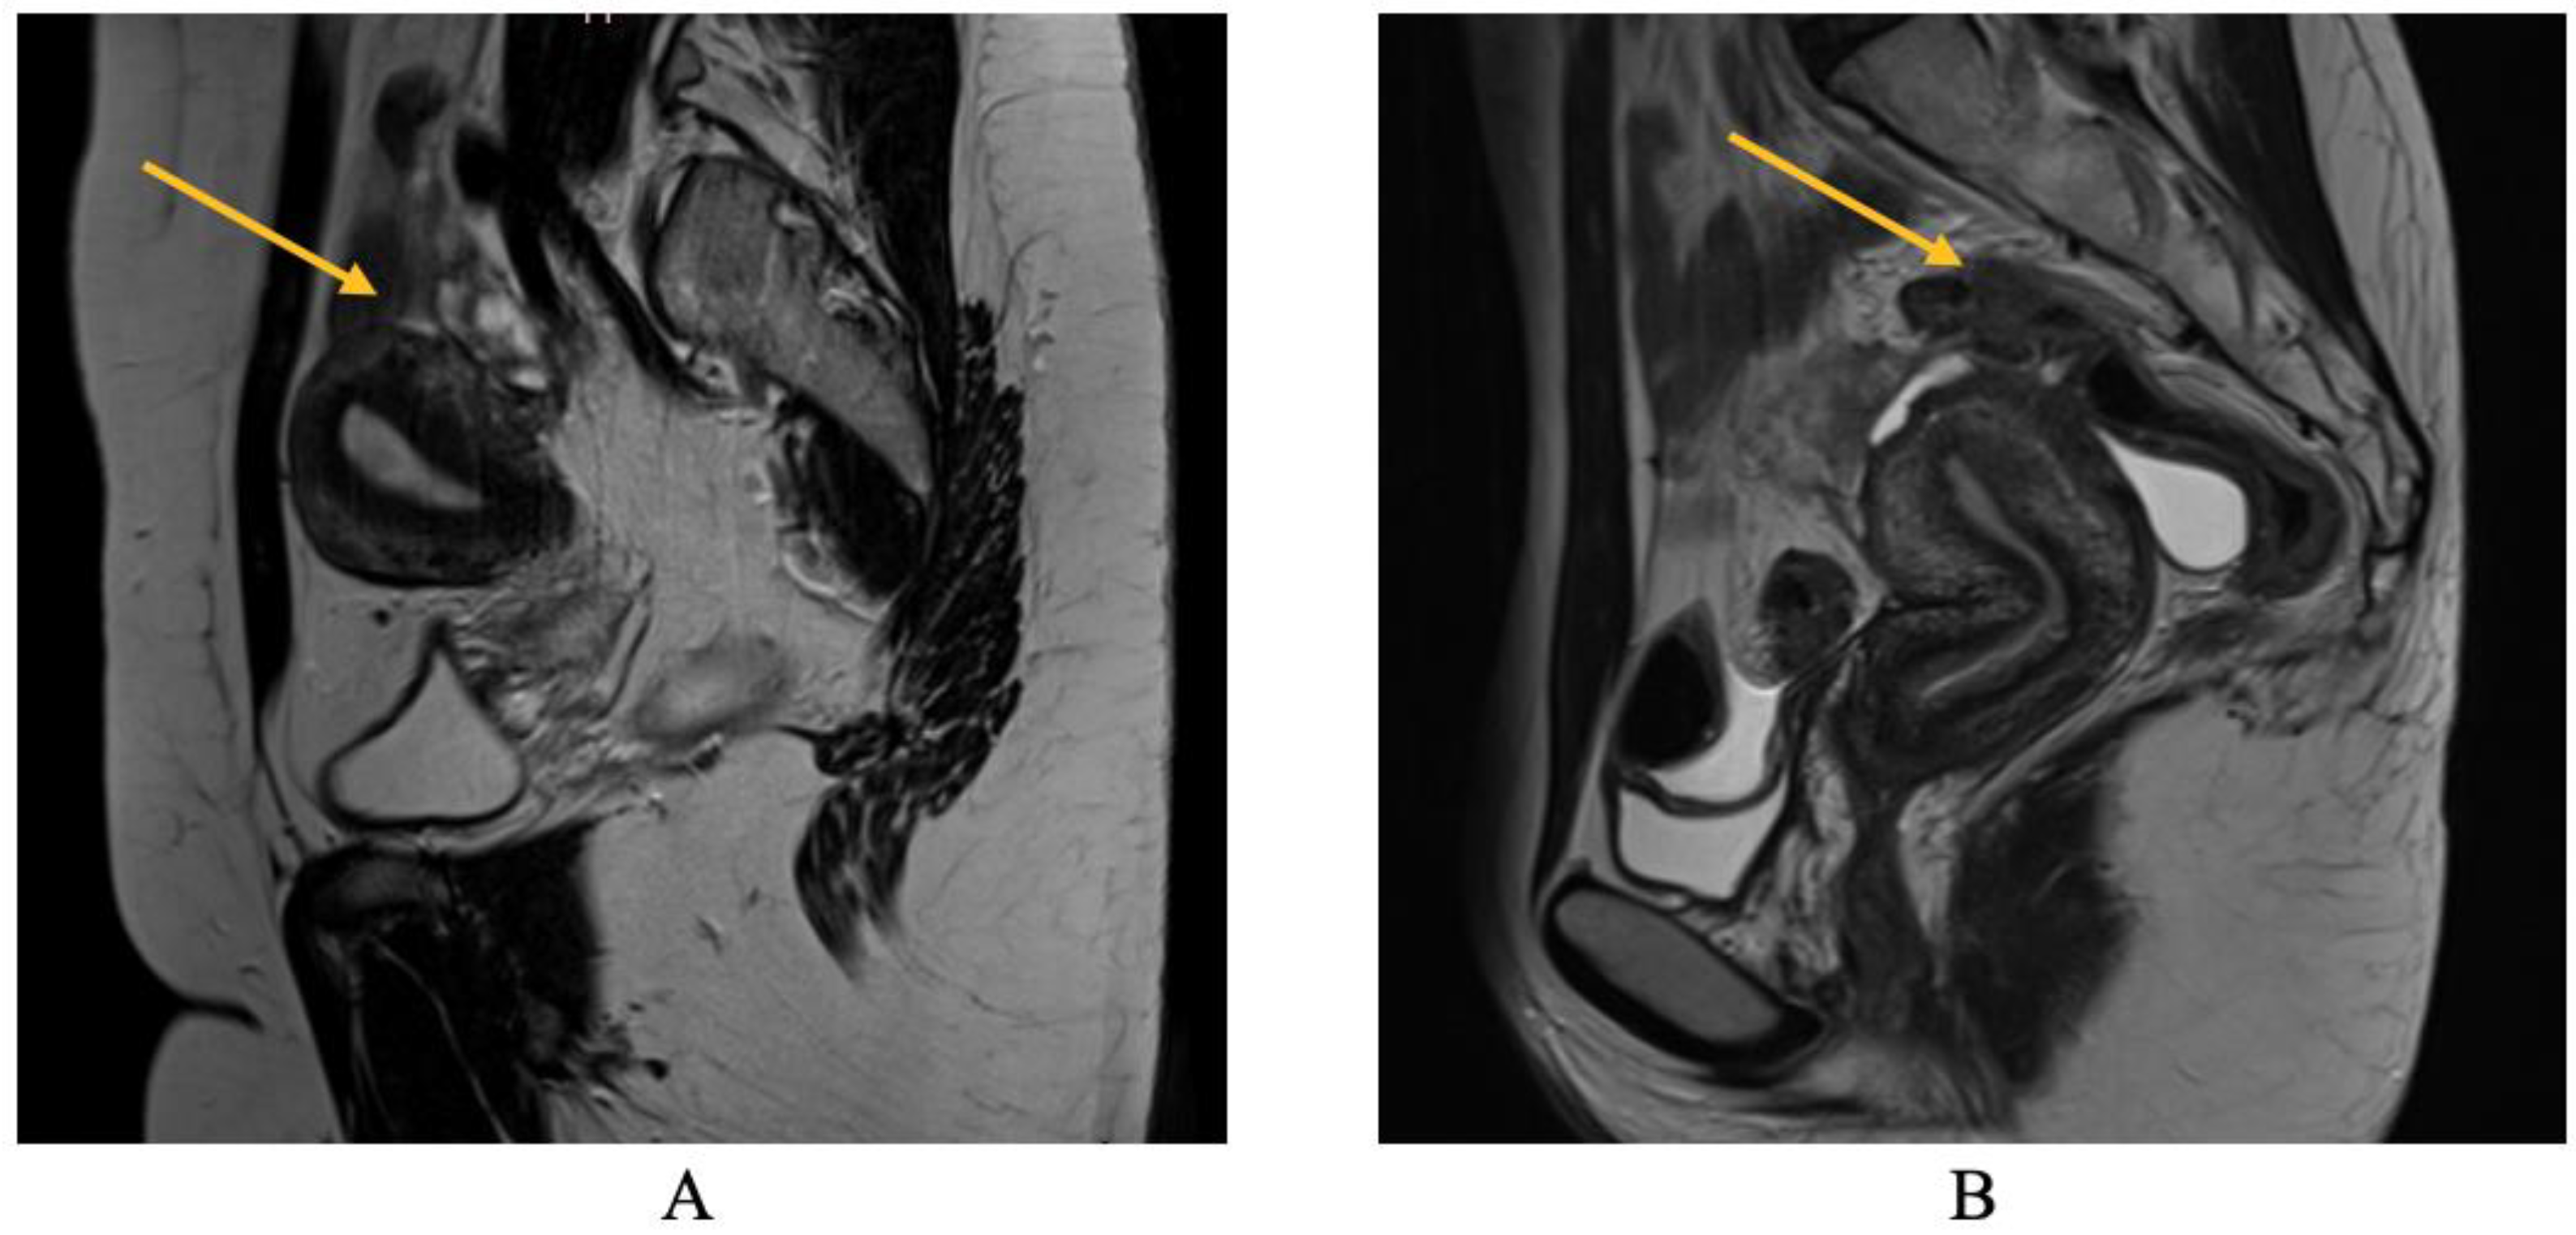

TVS is employed to diagnose bowel DIE by recognizing the thickening of the intestinal wall in a solid or plaque-like approach, as well as the absence of visceral fat separating the recto-sigmoid and the uterine wall [17,18]. The findings are depicted in Figure 6, where the yellow arrow highlights the existence of a rectal nodule exhibiting a negative “sliding sign” and the asterisks indicate the length of the lesion. This sign denotes the absence of rectal mobility in relation to the uterus and the posterior vaginal fornix, suggesting the likelihood of adhesion and endometriosis lesions [17,18]. The adherence of the rectal DIE nodule to the uterine torus is illustrated in Figure 6B.

Regarding MRI diagnosis of bowel DIE nodules, Figure 7 illustrates the presence of nodular thickening, which leads to anatomical deformation of the intestinal loop. The rectal nodule is adherent to the posterior uterine wall through an adenomyosis lesion, as indicated by the yellow arrow. Rectal DIE nodules typically exhibit adherence to other DIE lesions, including uterine torus, USL, parametrial, or adenomyosis [13,14].

Figure 6. (A) TVS aspect of rectal endometriosis lesion, (B) TVS aspect of rectal endometriosis lesion adherent to uterine torus endometriosis lesion.

Figure 7. MRI aspect on T2 sagittal (A,B): recto-sigmoidian endometriosis nodule adherent to the uterine fundus via adenomyosis lesion.